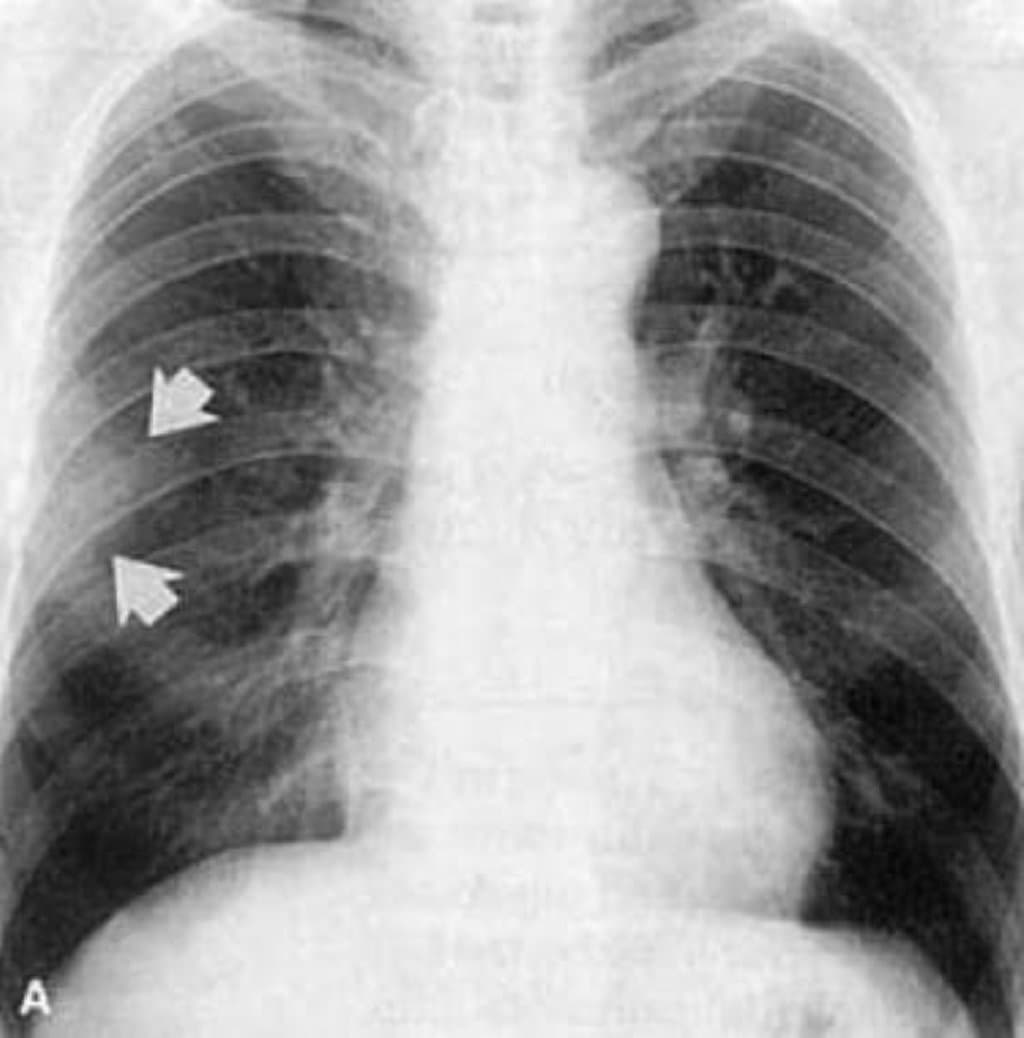

Löffler endokarditinin dəqiq diaqnozu üçün kardioloqlar tərəfindən kompleks müayinələr aparılır. İstifadə olunan əsas diaqnostik üsullar aşağıdakı cədvəldə göstərilmişdir:

| Exokardioqram | Ürəyin strukturunun və qapaqlarının ultrasəs müayinəsi. |

| Maqnit Rezonans (MRI) | Ürək toxumasının yüksək dəqiqliklə görüntülənməsi. |